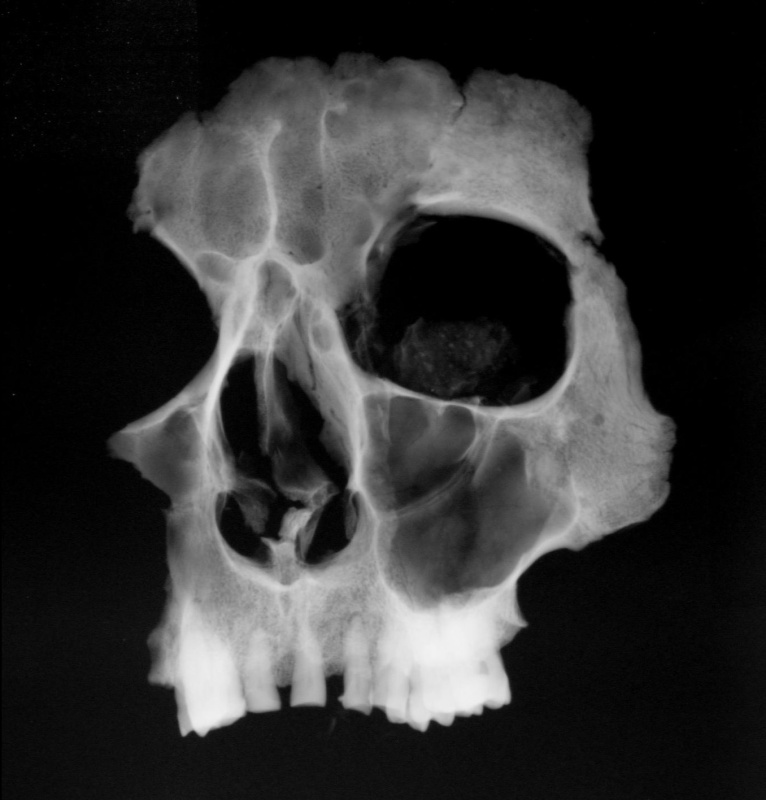

Biologický výzkum probíhal na pracovišti antropologického oddělení Národního muzea, kde byla provedena rentgenová, fotografická a morfologická dokumentace pozůstatků.

Po otevření kovové schrány s nápisem “Tycho Brahe 1901“se objevil obsah, který představoval sekundárně uložené kosti jednoho jedince (v neanatomickém sledu). V první fázi byly odebrány biologické vzorky s respektováním zásad minimalizace jejich kontaminace. Následně byl postupně vyjmut obsah schrány. Na dně rakve byl jako poslední uložen pohřební oděv. Kosterní pozůstatky byly poté sestaveny v anatomickém sledu, z kterého je patrné, že pravá horní polovina kostry je silně poškozená a není kompletní. Obsahem schrány byly rovněž dvě skleněné nádoby. Ve větší byly uloženy pozůstatky obličejového skeletu s vousy a autentifikační certifikát doc.Jindřicha Matiegky z roku 1901. Menší skleněná nádoba obsahovala zbytky organické hmoty.

V okolí nosního otvoru (apertura piriformis) byly nalezeny zbytky zeleného zbarvení, které popisuje Jindřicha Matiegka ve své zprávě. Zbarvení, způsobené přítomností měďnatých iontů, lze dávat do souvislosti s nošením nosního nástavce. Zranění nosu a nosních kostí, které astronom utrpěl v boji, není viditelné pouhým okem.